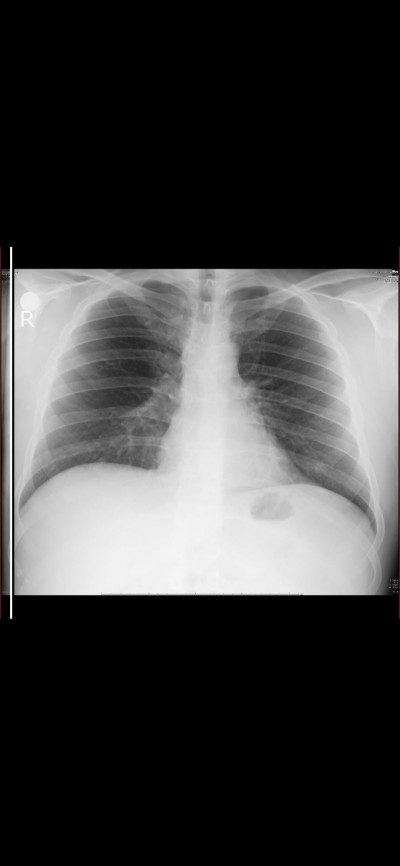

biliyorum şimdi raporda herşey normal yazıyor okuman yazman yok mu diyecksiniz ama

Yuvarlak bi siyahlık varr o ne acaba

Şuan internetten baktım normal akciğer filmi görüntü diye eşimin kinin aynısı çıktı ayni yuvarlak bişey var demmeki normal ama acaba ne ordaki herkeste olan

Kız o fundus gazı. Ciğer başka yerde leke dediğin şey başka yerde.

Mide gazı canım o yuvarlak şey :woot: her şey normal geçmiş olsun